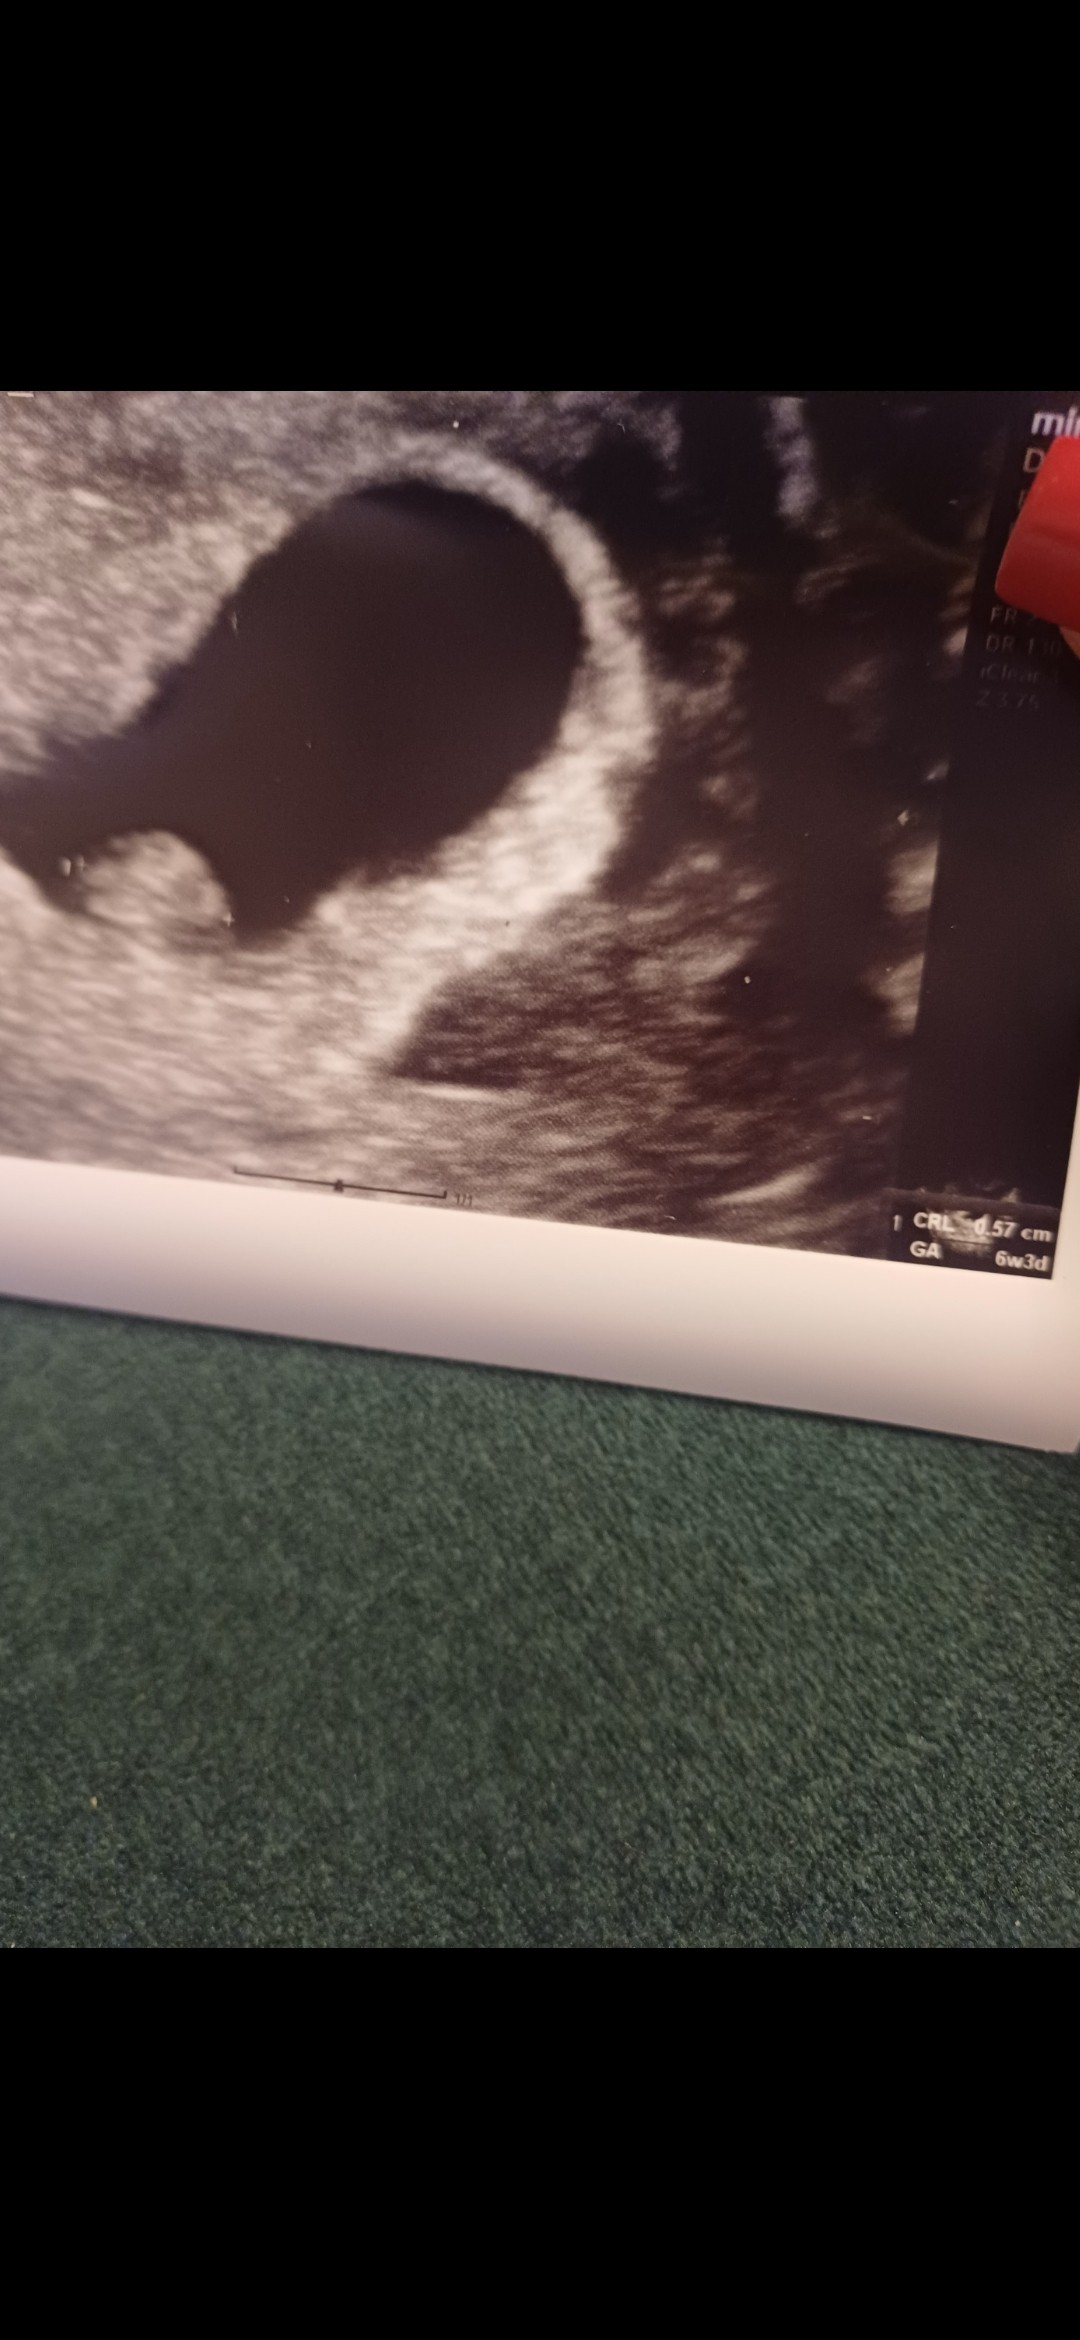

Hejka, ja po wizycie. Jest zarodek i serduszko. Termin mam na dzień mamy

Dziś 6t3d. Więc pewnie rozpakuje się na końcu bo córkę miałam porod wywoływany w 41 tygodniu 😅